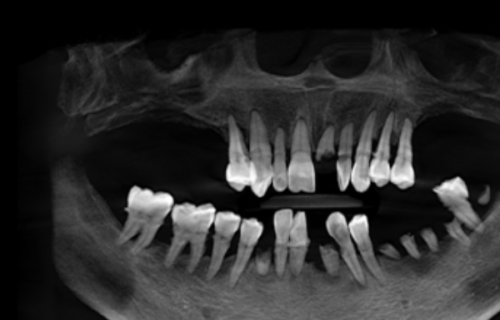

在种植牙手术前,医生会详细评估患者的口腔健康状况。这一步非常重要,因为只有确保种植条件成熟,才能为手术的顺利进行和减少痛苦奠定基础。医生会检查患者的牙齿、牙龈、牙槽骨等情况,看看是否存在炎症、龋齿等问题。如果有,会精良行相应的治疗,等口腔状况达到适合种植的标准后,再进行手术。这样可以避免在手术过程中因为口腔问题而增加痛苦,也能提高种植牙的成功几率。所以,手术前的评估和准备是减少痛苦的关键一步。